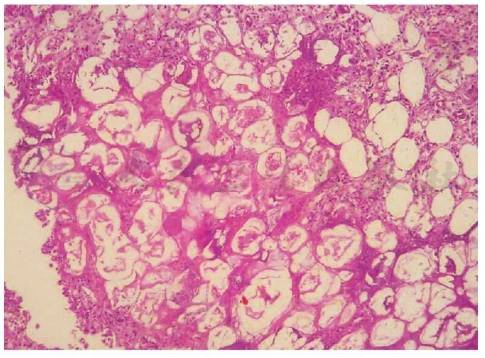

期可表现为间隔脂膜炎,间隔内血管扩张,胶原纤维增生,有淋巴细胞、中性粒细胞、多核巨细胞、少许嗜酸性粒细胞等浸润。后期逐渐出现间隔-小叶混合性脂膜炎。脂肪细胞凝固坏死,胞核消失,细胞壁变模糊,增厚,形成特征性“鬼影细胞”。脂肪被钙盐皂化生成嗜碱性物质,呈颗粒状或均质状沉积。病程晚期纤维化,脂肪组织萎缩(图1~图3)。

图1胰腺性脂膜炎病理(一)

引自:朱德生皮肤病学.第5版.ISBN:978-7-117-29665-6.主编: